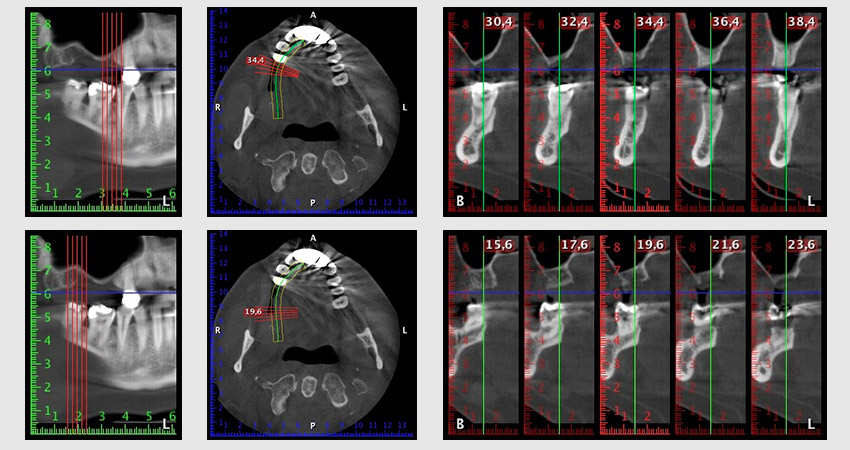

To restrict the augmentation to region 14, and in consultation with the patient, it was planned that implant 16 would be placed, inclined, in the dorso-cranial direction (Fig. 8).

Image 8: DVT with plan of insertion angle for implant 16